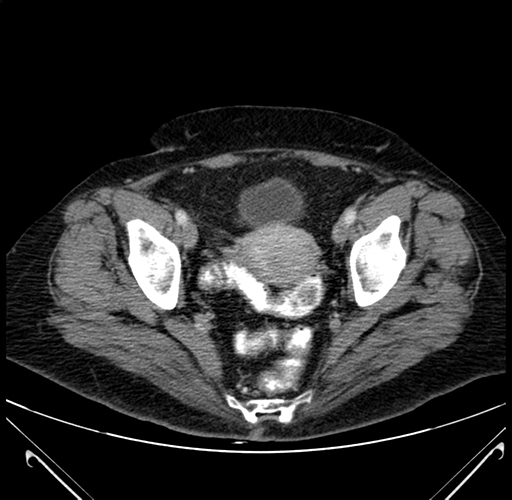

Pre-Chemo: Axial Venous

Axial Venous